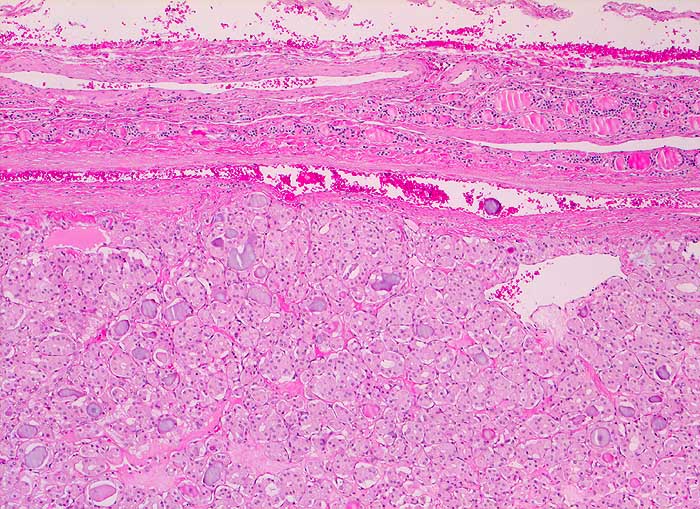

Mikrofollikuläres Schilddrüsenadenom

Punktate aus mikrofollikulären oder trabekulären Adenomen sind zellreich und kolloidarm. Die Thyreozyten bilden oft Mikrofollikel oder kleine Rosetten, die eosinophile Kolloidtropfen umschliessen. Die Kerne sind gleichförmig rund, fein granuliert und zeigen keine Atypien. Gelegentlich finden sich regressive Veränderungen. Zytologisch sind follikuläre Adenome und hoch differenzierte follikuläre Karzinome nur schwer zu unterscheiden. Aus diesem Grund werden beide Läsionen mit dem Begriff "follikuläre Neoplasie" bezeichnet. Unten sind zwei Beispiele von mikrofollikulären Adenomen abgebildet.